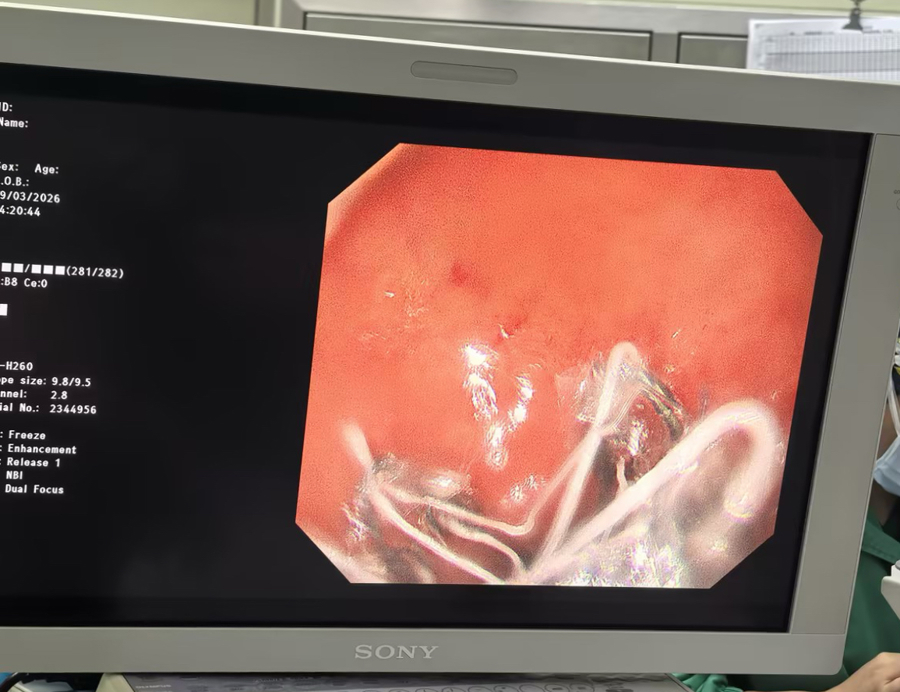

术中,团队借助先进的内镜建树,精确地将长约60cm的胃转流支架置入十二指肠及空肠上段,从而遮掩食糜和十二指肠/近段小肠黏膜,减幼年肠绒毛上皮细胞对养分的经受。手术获胜开展,全程患者人命体征平稳。术后第四天,患者获胜出院。3个月后,翌日院行胃镜下胃转流支架取出术。